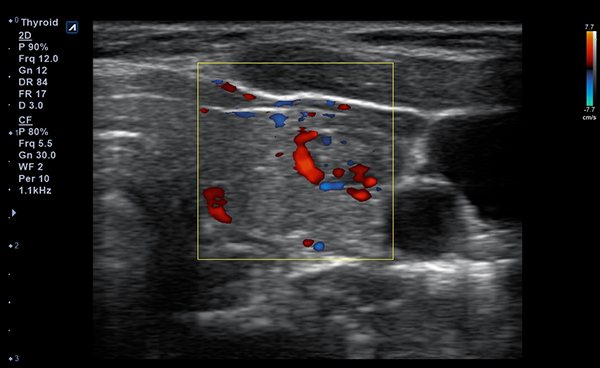

Alpinion Medical Systems, la empresa de sistemas de ultrasonido, ha combinado tecnologías

de procesamiento de imágenes y transductores para garantizar que minisono proporcione

imágenes 2D de alta definición e información de Doppler más claras y nítidas.

minisono ofrece funciones esenciales con el nivel de rendimiento necesario

para garantizar que los exámenes y diagnósticos sean precisos.

- Imaging modesB-mode, CF, M, PW, PD

- Frequency3-12 MHz

- Dimension (height/width/depth)25.2 / 62.5/ 150mm

- Weight 175g

- Field of view 38.4mm

- Max depth10 cm

- DisplayMicrosoft Surface

- Battery300 min